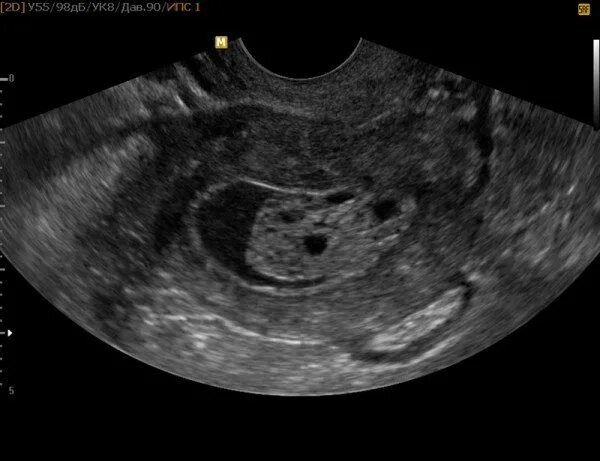

Серозометра лечение